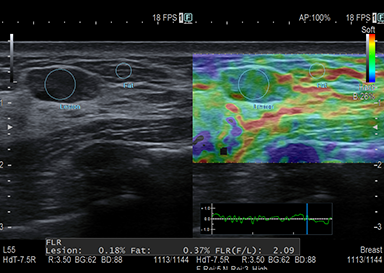

肝硬度・線維化・脂肪化測定

Shear Wave Measurement(SWM) / Attenuation計測(ATT)

組織にせん断波を発生させ、伝搬速度(Vs)を計測することで硬さを定量的に評価できます。肝脂肪化の程度を推定するための指標(ATT)も同時に計測します。

慢性肝障害のある方・脂肪肝がある方